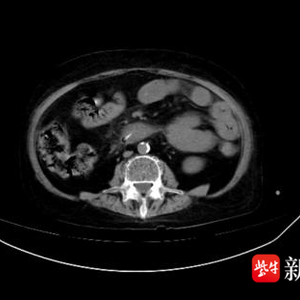

近日,南京市民徐先生因腹部疼痛难忍被紧急送往南京鼓楼医院江北院区消化科就医。主治医师马晓蕾立刻为徐先生安排了急诊腹部CT扫查,在患者十二指肠水平部发现一枚细长的致密影。马晓蕾仔细与患者家属沟通病情,交流中患者家属猛然回忆起,剧烈腹痛前,徐先生曾喝过一碗鸡汤。与CT结果对比,马晓蕾医师基本确认患者十二指肠水平部异物是喝汤时不慎吞下的骨头。

腹部CT显示十二指肠内异物

根据CT显示,异物周围的肠管已经发生了明显的渗出,甚至产生了可疑的包裹积气,说明鸡骨可能穿透了肠道!与此同时,患者的腹痛愈演愈烈,还出现了发热,腹部因疼痛而不能触碰,医学上称之为腹膜炎体征,提示感染向腹腔蔓延。